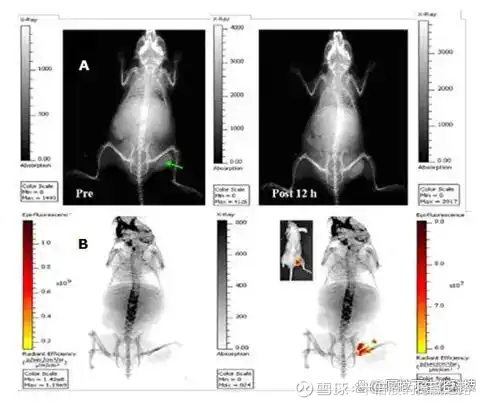

图 8:(a)瘤内注射负载吲哚菁绿的二氧化硅包覆金纳米棒(200μL, 1.5 mg/mL)前和12 h后小鼠体内平面X射线图像(曝光时间30 s);(b)瘤内注射双模成像造影剂12 h后60 s曝光时间(左)的体内平面X射线图像与对应的近红外荧光图像(10 s曝光时间)(右)重叠。插图:亮场与近红外荧光图像的对应叠加。绿色箭头表示肿瘤。夹在金纳米棒和吲哚菁绿发色团之间的薄层二氧化硅保护染料免受荧光猝灭。